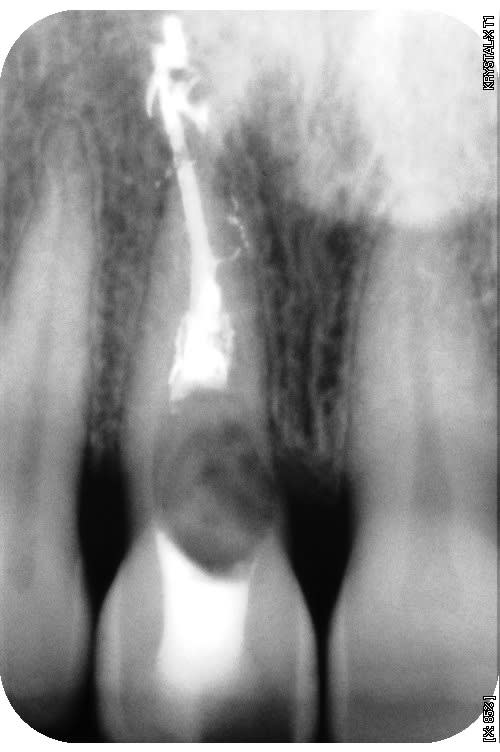

une autre radio qui explique un peu le dépassement, (enfin ça m'arrange de le penser) condensation trop forte pour avoir aussi les canaux accessoire.

--